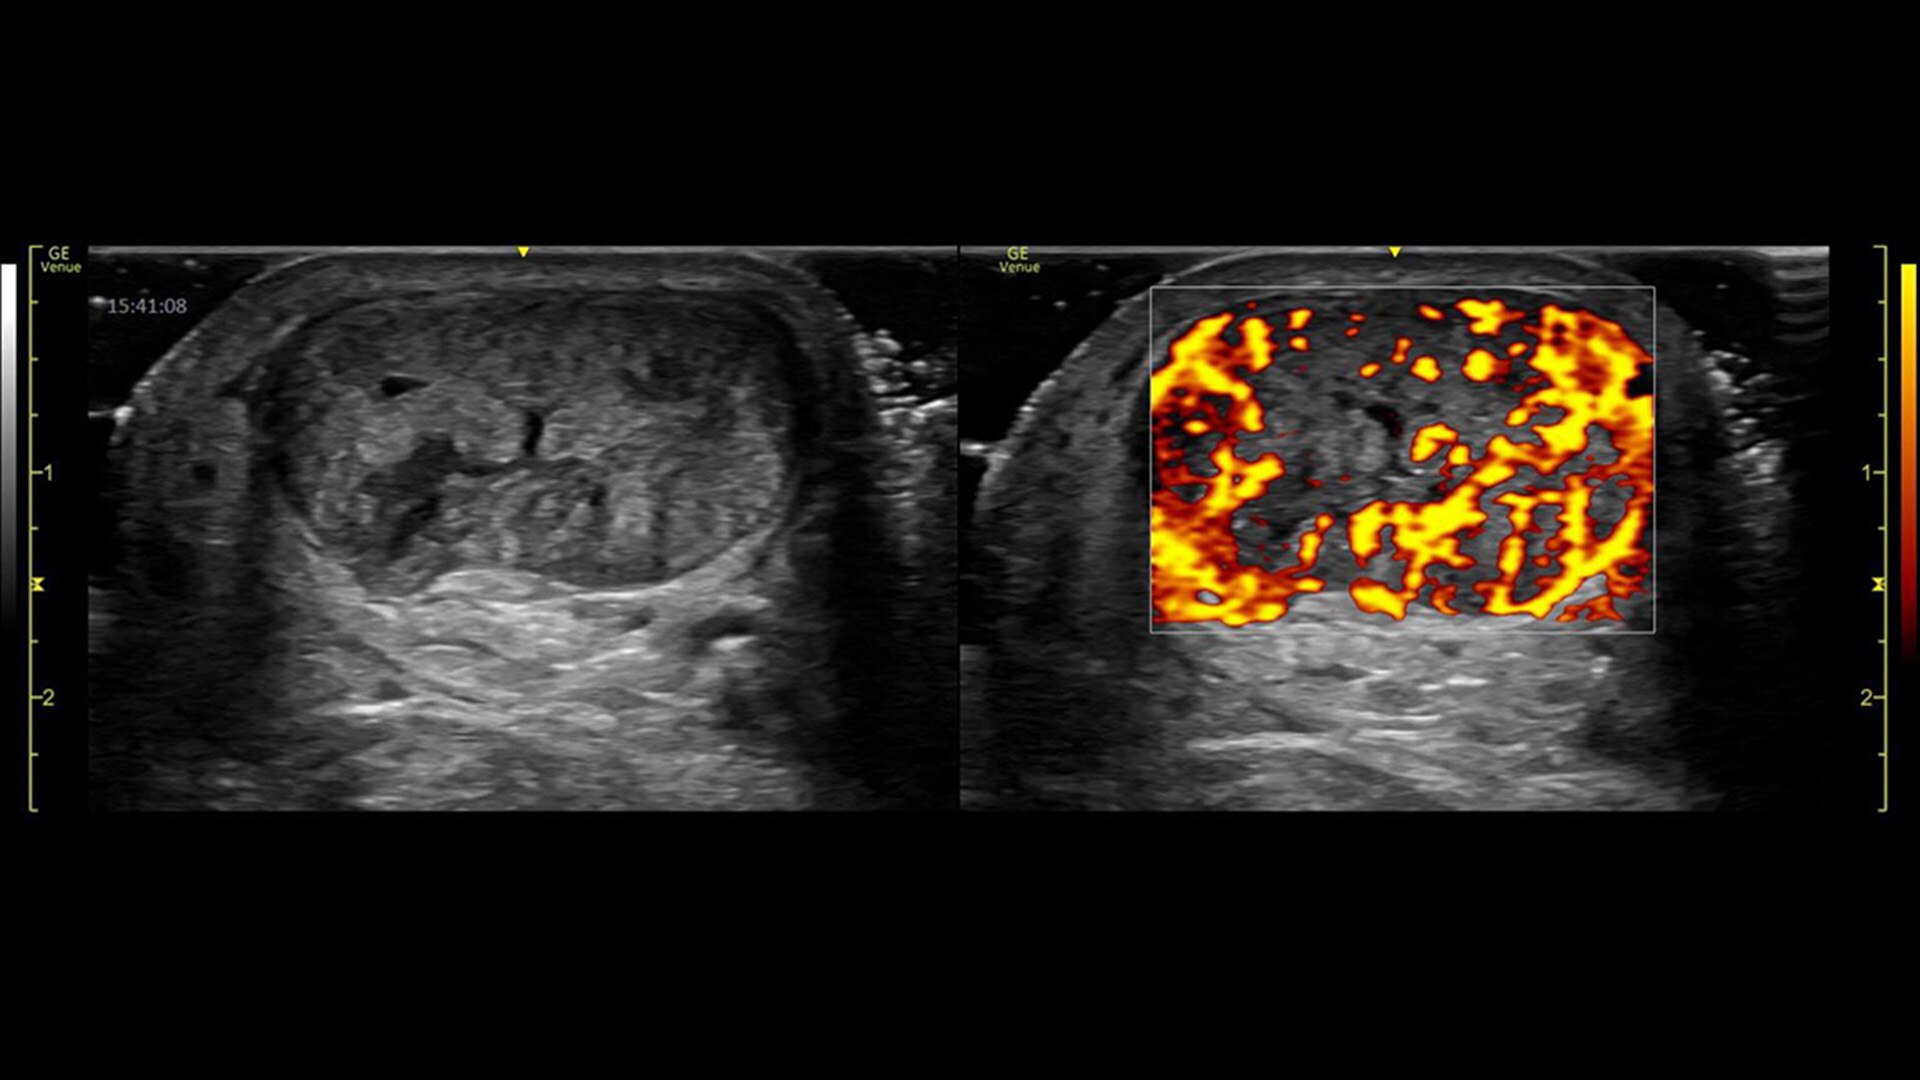

POWER DOPPLER IMAGING

Visualize slower blood flows

Power Doppler Imaging + (PDI+) is a color flow mapping technique used to map the strength of a Doppler signal coming from the flow rather than the frequency shift of the signal. In PDI+ mode, the sensitivity of the color in the Region of Interest (ROI) increases. Providing a higher resolution than the regular PDI mode, PDI+ is best used for slower blood flows such as those found in wrists, ankles, hands, and feet. This is an additional option that exists within the regular PDI mode.